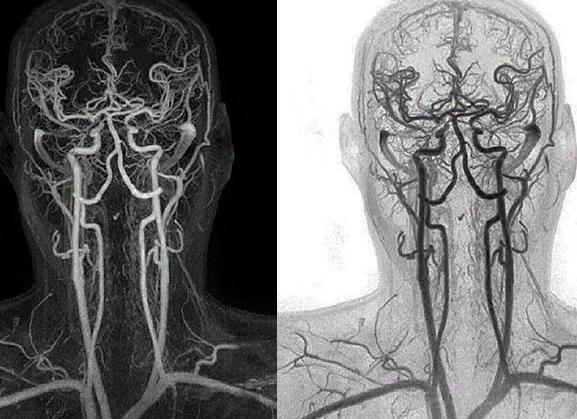

КТ ангиограмма может обеспечить двух- и трехмерные изображения кровеносных сосудов и сердца.

МСКТ сосудов головного мозга (исследование с в/в контрастированием) 12 000

МСКТ сосудов шеи (исследование с в/в контрастированием) 12 000

• Ангиография на томографе – метод изучения состояния вен, сосудов и капилляров. На основе данных, полученных после сканирования, выстраивается модель кровеносной системы в трехмерном формате. Это позволяет оценить проходимость сосудов и характер кровотока.